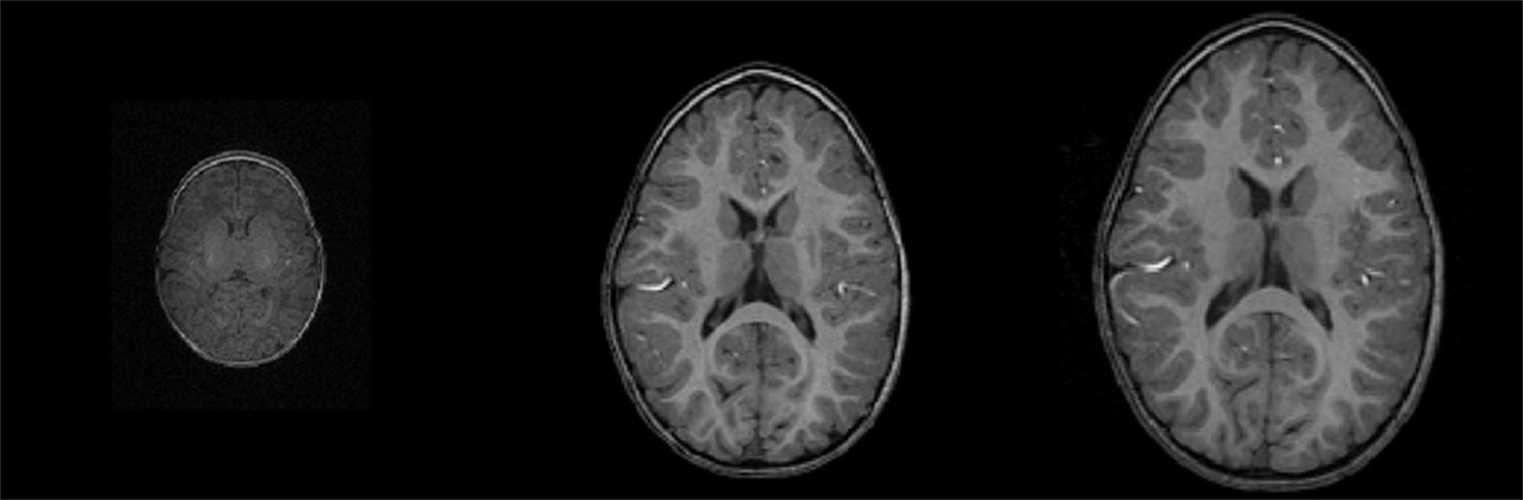

Three black and white MRI images show a child’s growing brain at birth, 1 year old and 2 years old.

A series of MRI images shows a child’s brain developing from birth (left) to 1 year old (center) and 2 years old (right). Credit: Journal of Neuroscience

For example, one of the phenotypes, or characteristics, researchers will be observing is the size of a child’s brain and how it grows.

“Total brain volume increases dramatically for the first two years of life and then levels off,” Knickmeyer said. “With this study, we can look at, OK, this is volume at birth, this is how big the brain gets and this is how quickly it gets there.” Connecting such information to behavior and genetics could help doctors recognize signs of disorders earlier in life and open up new opportunities for treatments.